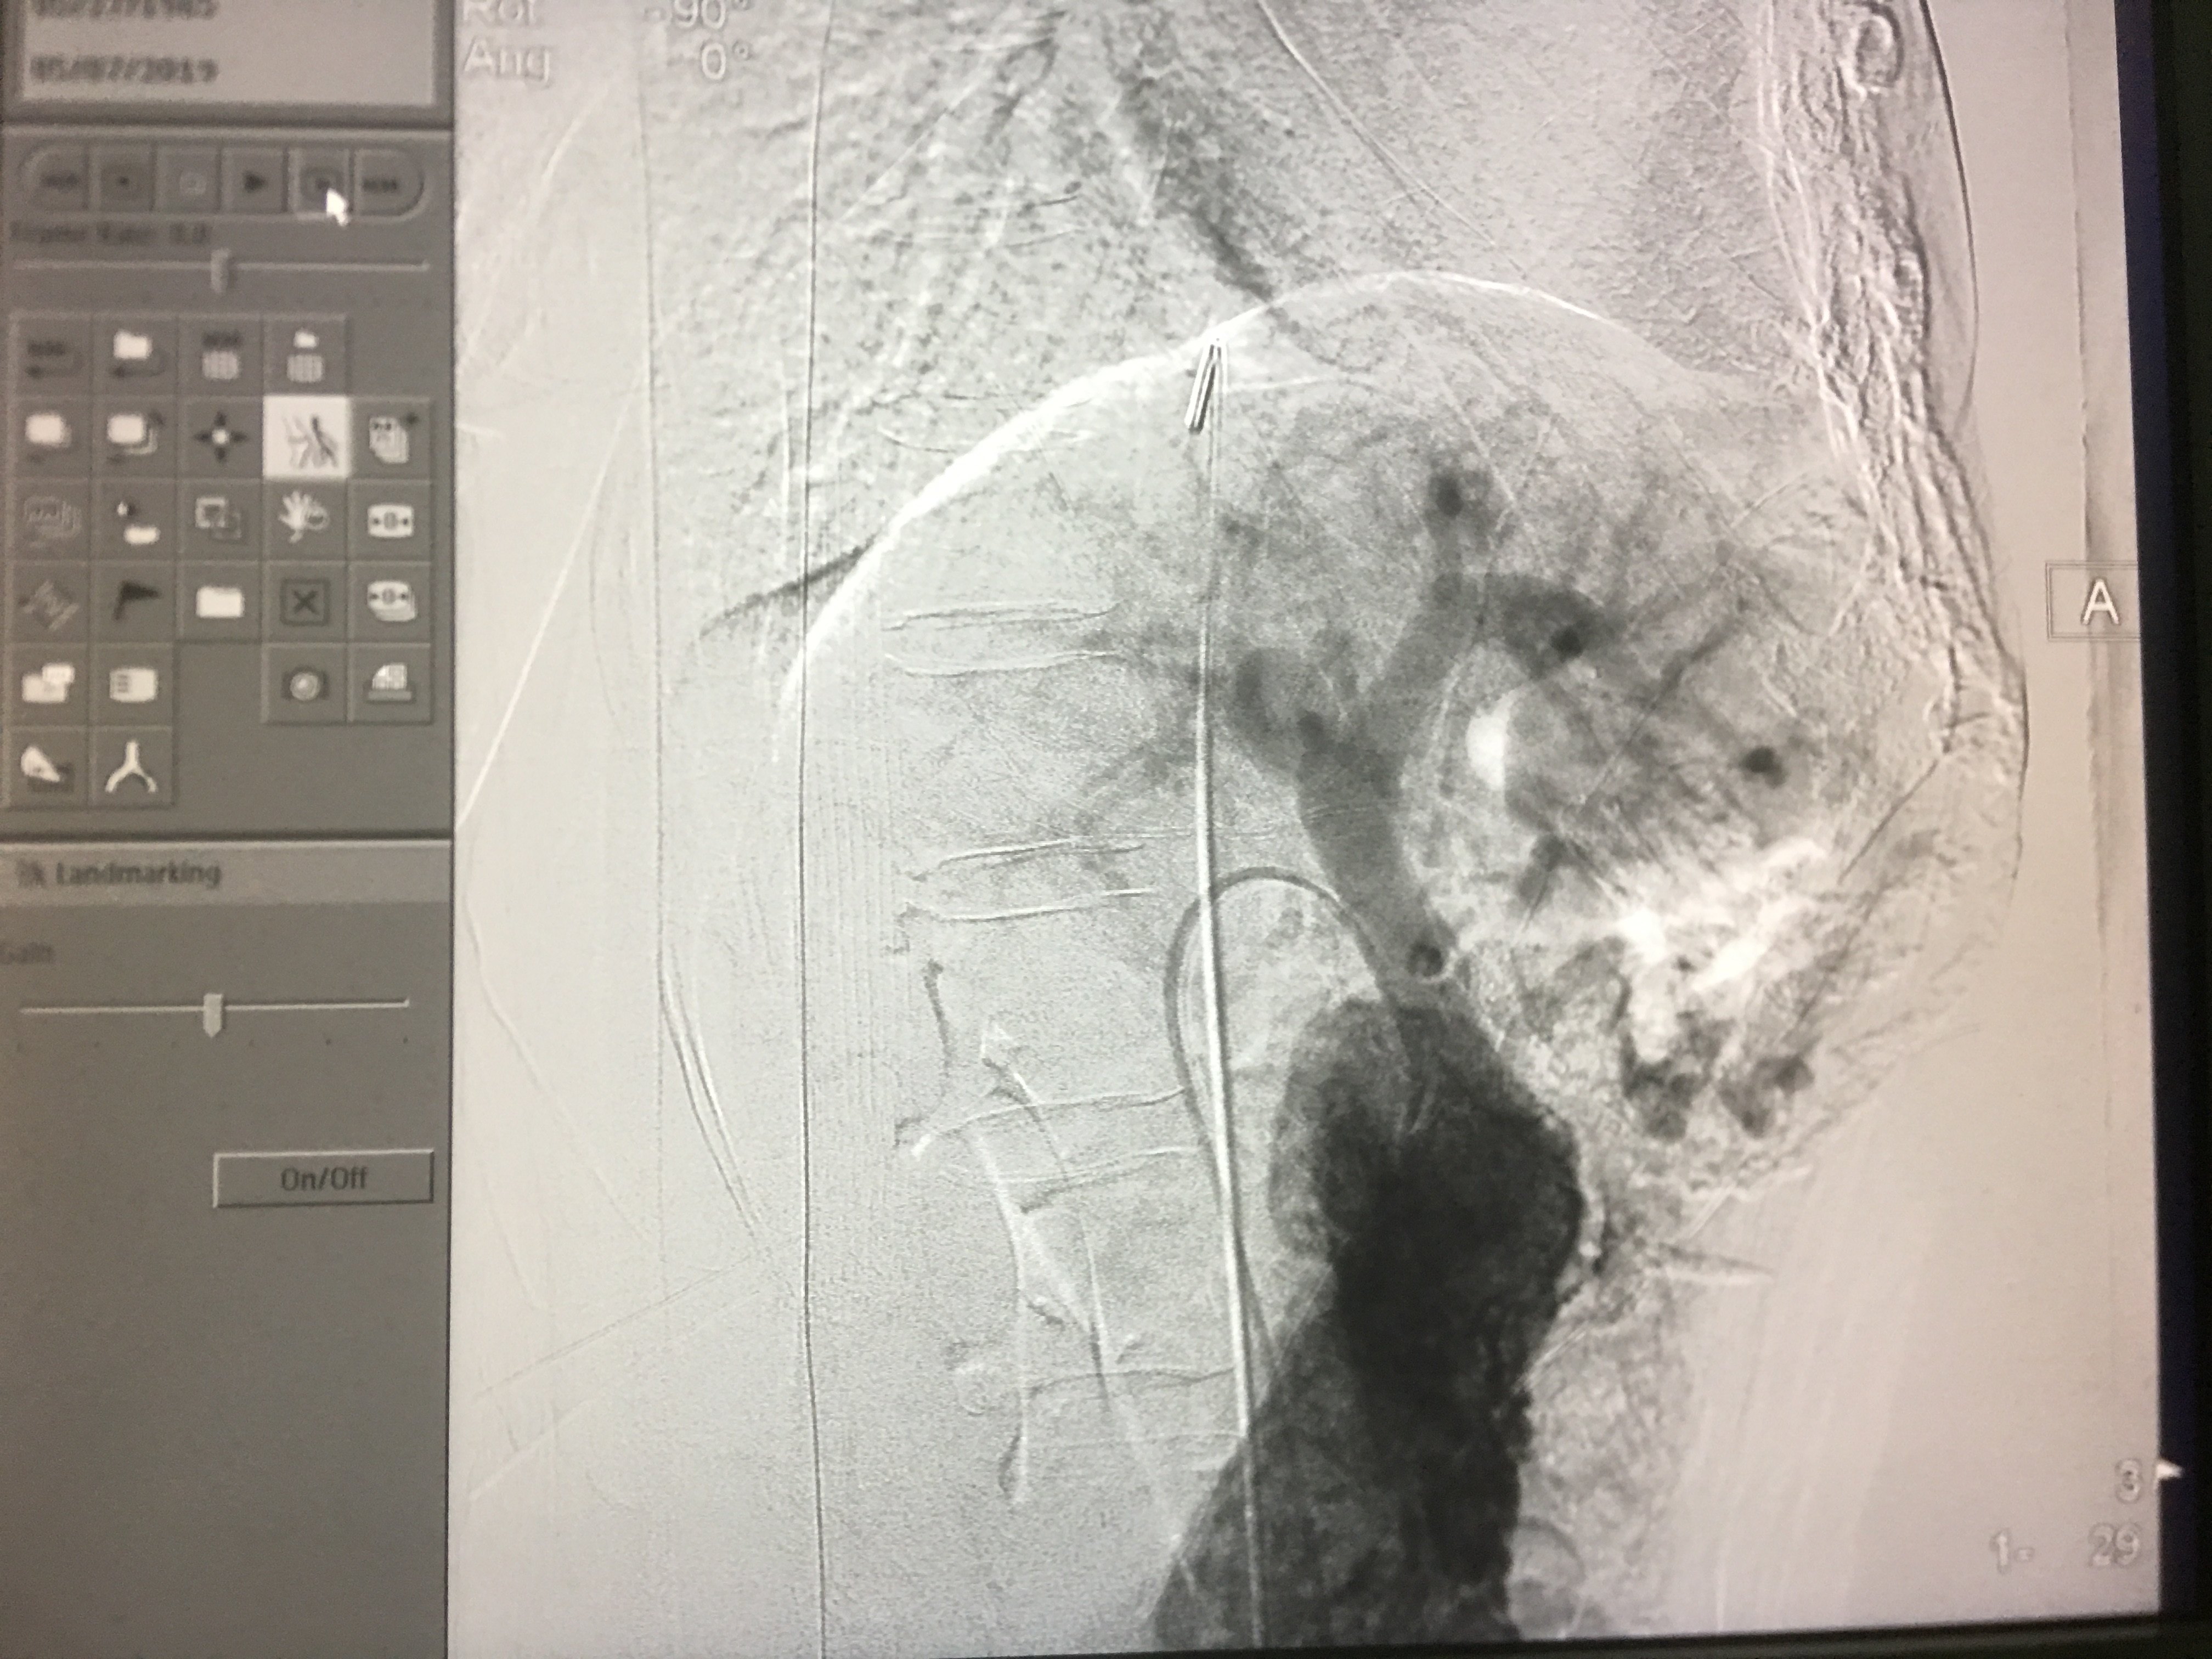

调整角度穿刺成功后进行直接门静脉造影,测门静脉压力。